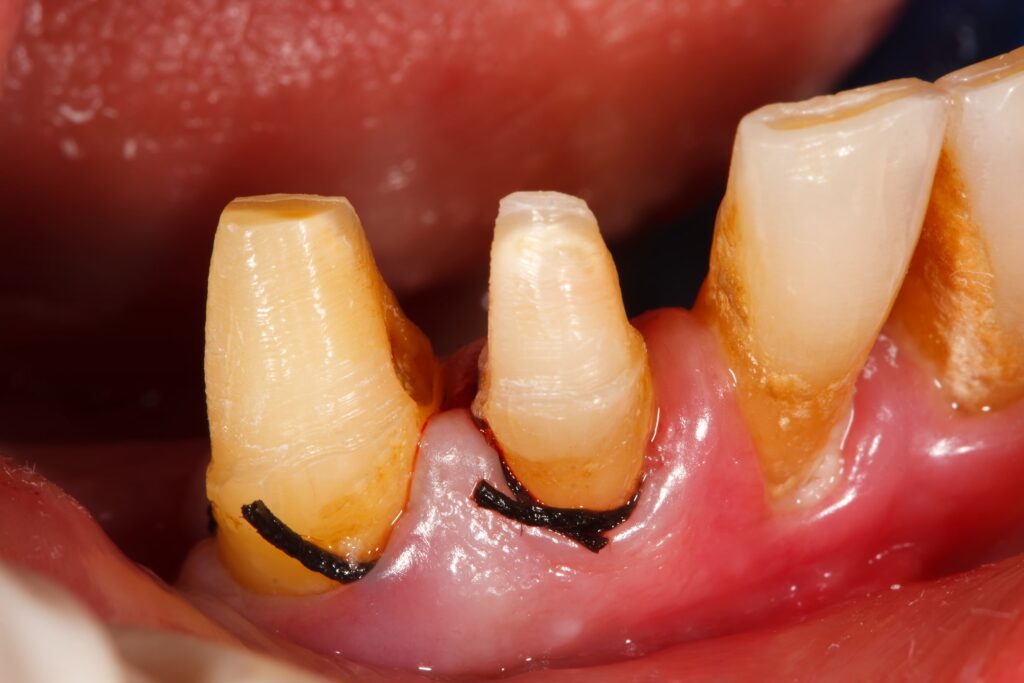

Cum recunoști retracția gingivală – simptome clare

Semnele care indică o problemă gingivală includ:

- Sensibilitate crescută la rece sau cald.

- Expunerea rădăcinii dintelui, dinții par mai lungi.

- Inflamație, roșeață și sângerări gingivale.

- Curățare profesională profundă (detartraj ultrasonic și airflow) pentru eliminarea tartrului și a bacteriilor.

- Tratament laser sau PRF (Platelet Rich Fibrin) pentru regenerarea țesutului gingival.

- Grefe gingivale sau chirurgie plastică parodontală în cazurile severe, unde gingia trebuie reconstruită.